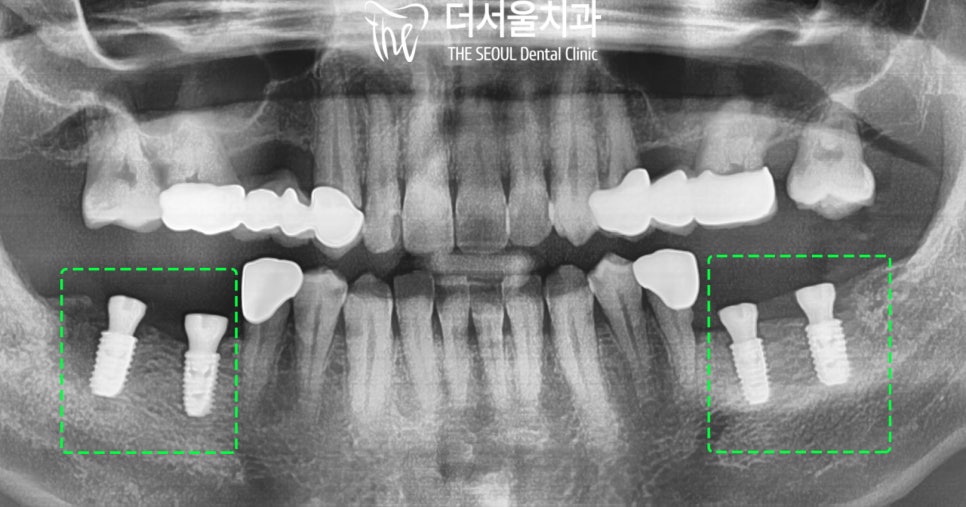

【 결과 】

단대오거리역 치과에서는

잘 심어졌는지 x-ray를 통해

한 번 더 확인했습니다.

성공적으로 잘 들어갔습니다.

이제 골 유착을 하는 시간을 가져주는데요.

그 후 골 결합이 잘 이뤄지고

다음 단계인 보철 제작에 들어갔습니다.

그리고 보철이 완성되고

환자가 다시 방문하셨는데요.

실제로 적용된 모습을 보면,

튼튼한 어금니가 생겨

이제 편안한 식생활을 가능하게 해줍니다.

기능, 심미성 모두 신경 써서

제작해 드렸습니다.

x-ray로 최종 확인까지

진료 마무리했는데요.